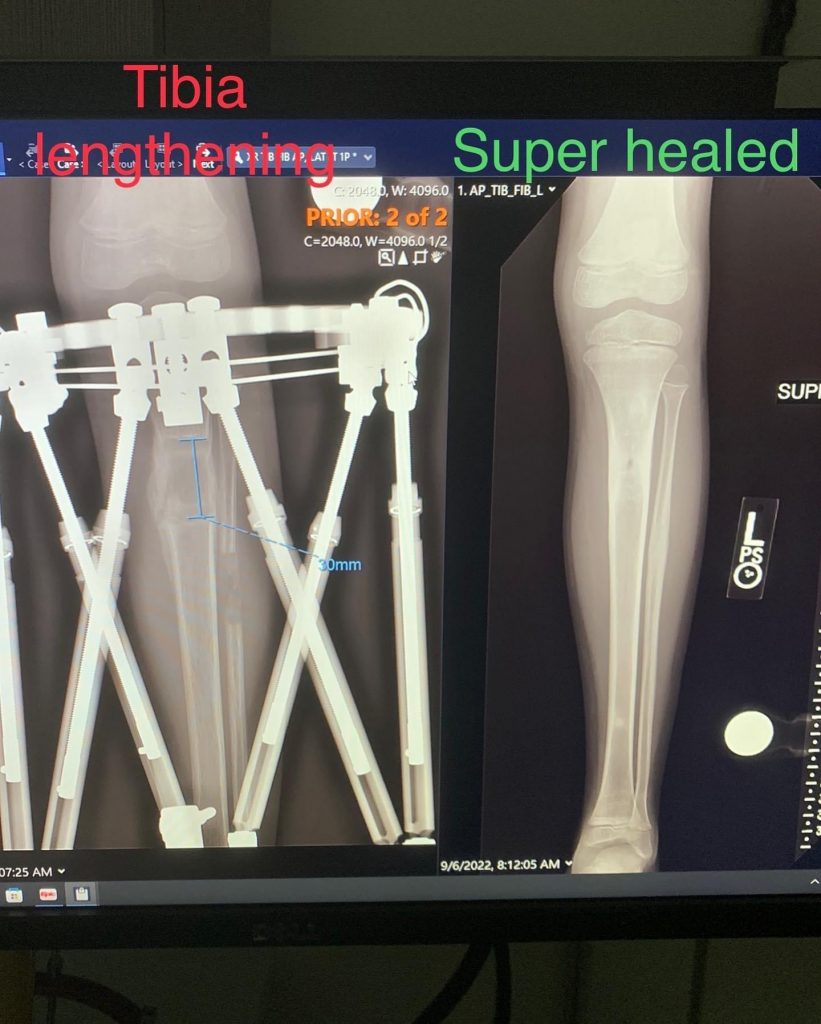

Legs can be lengthened one of two ways – by inserting a rod into the bone and using magnets to lengthen the leg or by attaching an external fixator to the outside of the leg and turning the struts (or screws if you will) to lengthen the leg. The surgery Reid experienced was the attachment of an external fixator. Dr. Rozbruch and his operating team first break the leg bone being lengthened (in Reid’s case, his tibia) and then attach the external fixator using a combination of screws and pins. The pin sites (where the pins meet the skin) must be kept clean and infection-free. The struts (or screws) are turned ever so slightly a few times a day for a handful of weeks (called the Lengthening period). The broken leg bone begins to heal during this period, but not enough to disturb the lengthening. Once the struts have reached the necessary length, the leg has been successfully lengthened and the bone accelerates its healing process now that it is stable and no longer being stretched apart vertically.

Reid’s lengthening period was approximately 4 weeks, and during this time he was required to do several home stretching exercises 3 times a day in addition to outpatient physical therapy at HSS 3 times a week. He initially started out using a wheelchair, but quickly progressed to a walker and then to crutches. Within days of surgery, Reid was walking with the support of a walker, slowly and infrequently at first, but then as if nothing was holding him back. Because Reid has continued to take growth hormone for his RSS condition, the healing process of the broken tibia was not as challenging as it would have been for someone not taking growth hormone. The hardest part of Reid’s recovery was strengthening and lengthening the leg muscles that were affected by the bone lengthening. After 4 weeks away from home, we came home to continue Reid’s recovery.